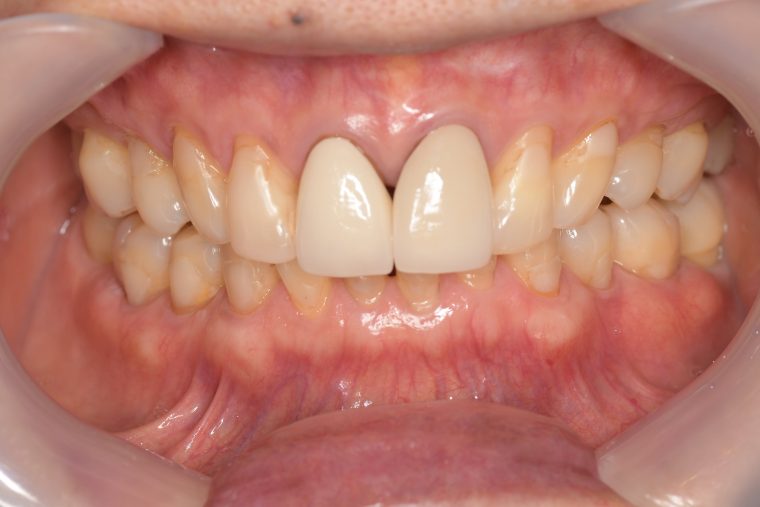

Before

症例

年齢・性別 75歳・女性

主訴 主訴:左上奥の歯ぐきが腫れた

治療部位:左上下奥歯、右下奥歯

治療内容 1.歯周ポケット検査、歯磨き指導、抗生物質塗布

2.縁上の歯石除去

3.縁下の歯石除去

4.再評価

5.定期検診(3ヶ月おき)

→内容:口腔内写真、歯周ポケット検査、歯磨き指導、歯石除去、着色除去(PMTC)、フッ素塗布、ドクターによる虫歯のチェック、ナイトガードのチェック

治療期間 3ヶ月

治療費 定期検診の合計:3,210円(保険診療3割負担)

(2022年8月現在)

リスク・副作用 定期検診は個人によって期間を変えています。

ご自身での管理が困難な方や歯周病や虫歯のリスクが高い方は1ヶ月おきにクリーニングをしています。

その都度患者さまとご相談させて頂いた上で期間を決めさせて頂いています。

特記事項 ・65年前に矯正治療をしてから歯をずっと大切にしてきたので、なるべく抜歯はしたくない。

・上の前歯は10年前にお孫さんがぶつかってきて、神経の治療をした。

・食いしばりをする癖がある為ナイトガード(夜間につける歯を保護するマウスピース)を作製し使用して頂いている。

担当者所見 左上は歯ぐきがかなり腫れていたが、歯石除去とホームケア(歯ブラシ、歯間ブラシSサイズ、ミクリンタフトブラシ)と抗生物質(軟膏)により腫れが落ち着いた。

それに加え、過度な力がかからないよう、ナイトガードを毎日使って頂くことと、日中の食いしばりにも気をつけてもらうようにした。

これは上の前歯を守るためのものでもあるので、必ず使用して頂いています。(上の前歯は神経がない為栄養が行き届かないので神経がある歯に比べ脆く根っこにヒビが入りやすい)

そして現在は定期検診で毎回異常がないか確認し、ホームケアではなかなか届かない歯周ポケット内のクリーニングを行っています。一度骨が溶けてしまっている為、歯周ポケットは残りますが、その後再発することは今のところなく、定期検診で今後もしっかり管理していきます。